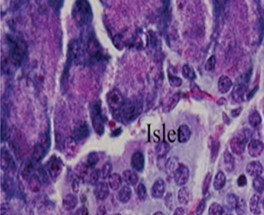

No comparable significant change observed in the mean weights of the extracted pancreas. The photomicrographs (Figure 4, Figure 5, Figure 6 and Figure 7) of the pancreatic tissue histology revealed preserved histoarchitecture in DSE and DEE groups as compared with the normal appearance of pancreas histoarchitecture from a normal healthy Wistar rat. Photomicrograph of the pancreas from diabetic control (DC) rats (Figure 7) shows distorted Islet margin with lymphocytic cells infiltration and moderate necrotic parenchyma.

Figure 7.Photomicrograph of the pancreas from diabetic control (DC) rats showing distorted Islet margin (arrow) with lymphocytic cells infiltration and moderate necrotic parenchyma (H &E stain X400 magnification)

Due to different species of garden egg in nature, likelihood of variation in its effect on weight reduction is expected. There is an uncited claim by some nutritionists that green garden egg species works better for weight loss compared to other species. However, findings obtained in our study using the white species with green stripes (S. aethiopicum L) revealed a remarkable reduction in weight gain in diabetic rats. Though, our present study did not compare species effect on weight gain, in our subsequent research however, we shall conduct a study to correlate species and weight-lowering effect. Meanwhile, based on the present outcome of this study, recommendation of the white-with-green-striped species should be encouraged for beneficial optimal effect on weight reduction. The beneficial impacts of S. aethiopicum on glycemic status and profile are depicted in Table 3 and Figure 2. The mean FBS concentrations decreased significantly (P < 0.05) in both DEE and DSE groups (DEE >> DSE, P = 0.025) compared with the control. The observed difference in their values was similar in manner to its effect on weight gain. The glycemic tolerance improved remarkably in both groups. This antidiabetic potential may be attributed to a major phenolic compound called chlorogenic acid (5-O-caffeoyl-quinic acid; CGA) present in garden egg 13, 21. Bhaskar 13 and Plazas 21 studies revealed that chlorogenic acid possessed anti-obesity, anti-inflammatory, anti-diabetic and, cardio-protective properties. The incremental areas under the glycemic response curves of DEE and DSE rats decreased remarkably compared with the control (Figure 2). The postprandial glycemic response peaked at 30 minutes of glucose challenge in both groups. The TC, TG and LDL-C concentrations decreased significantly with corresponding significant increase in HDL concentration in DEE and DSE rats (Figure 3). However, the extract impacts more beneficial antilipidemic effect than the supplemented diet. This finding also suggests that the optimal antilipidemic effect can be derived when S. aethiopicum is consumed in fresh or raw form than in mixed meal. The antilipaemic effect of eggplants has been attributed to an important phytonutrient compound called anthocyanin found in abundance in the skin of the eggplant which was reported to improve lipid profile through lipid peroxidation and serum antioxidants concentrations increase 27. Besides this antilipaemic activity, anthocyanin has also been reported to play significant role against diabetes, neuronal problems, cardiovascular disorders, and cancer as well 30. The pancreatic tissues sections’ photomicrographs examined under high power magnification (x 400) light microscope revealed the effects of S. aethiopicum on pancreas histoarchitecture. Figure 4 shows the normal appearance of the pancreatic histoarchitecture obtained from a healthy non-diabetic Wistar rat. Comparison of the experimental grouped rats photomicrographs with the normal revealed that the histoarchitecture of the pancreas in DEE and DSE (Figure 5, Figure 6) rats were preserved with no visible pathologic changes while the photomicrograph of the pancreas from diabetic control (DC) rats (Figure 7) shows distorted Islet margin with lymphocytic cells infiltration and moderate necrotic parenchyma. Examining the histological consequence of any product prior to recommendation is very essential because histological analysis of target organs for pathological changes surveillance is necessary to enhance screening assessment of quality and safety of product prior to recommendation for human consumption 31